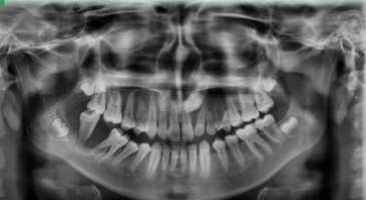

Fig 2: OPG showing large ill-defined expansile osteolytic lesion in relation to 46-48 region

Figure 6: solitary large ill-defined expansile osteolytic lesion of mixed density in the right body and ramus of the mandible

A 13- year old male patient presented with a painless rapidly enlarging growth of the right posterior region of jaw since 2 months. Intra-oral examination revealed a firm, non-tender reddish soft tissue mass in the right posterior mandibular region extending anteriorly from 45 to retromolar region posteriorly involving the buccal and lingual mandibular gingiva. Inferiorly the lesion extended till the floor of the mouth causing displacement of the tongue along with displacement of the associated teeth (Fig 1). Radiographically, an ill-defined osteolytic lesion of the right posterior mandible with buccal and lingual cortical plate expansion was noted (Fig 2).

A 14-year old female patient reported with an ulcerative lesion of the right posterior region of the jaw associated with mobility of teeth 46 and 47 since 1 month (Fig 5). The patient was apparently normal 1 month back after which the lesion was noted. CBCT shows a solitary large ill-defined expansile osteolytic lesion of mixed density in the region extending from 46 to the right body and ramus of the mandible (Fig 6). A provisional diagnosis of aggressive neoplastic lesion such as odontogenic myxoma and osteosarcoma was considered. Incisional biopsy was performed and the H and E stained sections shows sheets of malignant tumor cells separated by fibrous connective tissue septae. The malignant cells displayed atypical features such as cellular and nuclear pleomorphism, nuclear hyperchromatism and few bizarre shaped cells. Presence of eosinophilic areas resembling tumor osteoid surrounded by malignant osteoblasts was evident. In addition, the sections also showed a sub-population of clear cells which were round to oval in shape with vesicular nuclei and clear cytoplasm with some binucleation resembling chondroid like areas (Fig 7 & 8). Special staining for PAS and mucicarmine to rule out clear cell odontogenic carcinoma and intra-osseous mucoepidermoid carcinoma was negative. Based on these findings the final diagnosis was chondroblastic variant of osteosarcoma. Hemimandibulectomy was performed and the final diagnosis of the excised specimen was high grade osteosarcoma. Six month follow-up was uneventful.